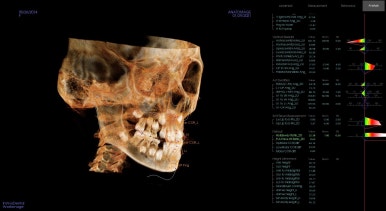

골연령(성장판 검사)과 골격 분석

또한 골격 분석을 하여 골격이 문제인지, 골격의 문제라도 단순히 앞뒤로의 문제인지 폭이나 높이의 문제는 없는지 등등 포괄적으로 분석합니다.

골격의 부조화가 심한 경우, facemask를 사용합니다.

이번 환자분이 사용하게 된 장치는 프리올소라는 장치인데요.

골격의 부조화가 크게 심하지 않을 때 + 치열도 어느정도 잡아주면서 혀/입술/볼근육 등 근기능의 연습이 함께 필요할 때 추천되는 장치인데요.